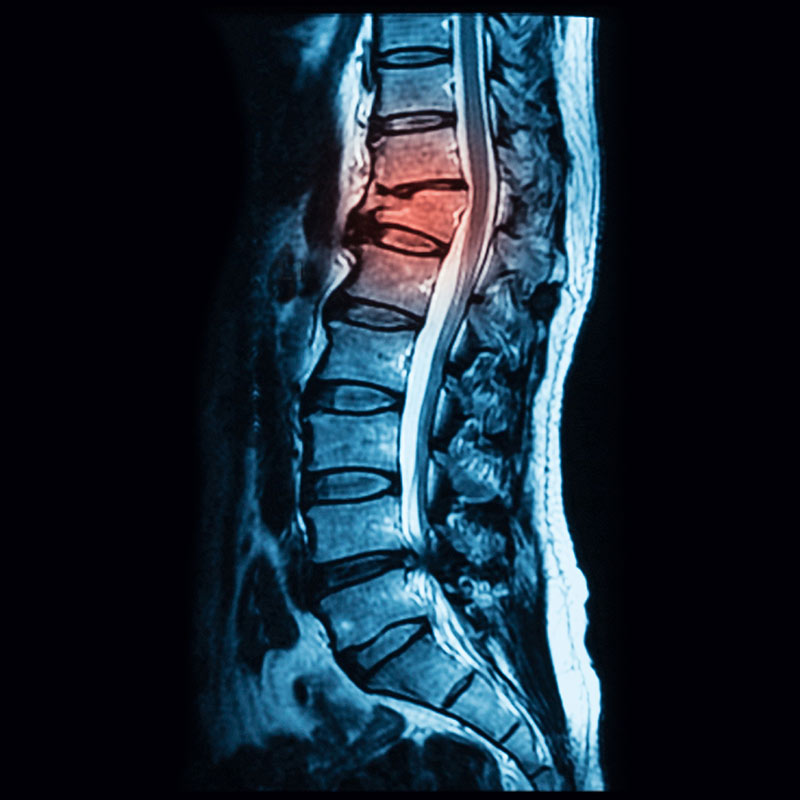

Querschnitt der Wirbelsäule von einem Röntgengerät betrachtet. Schmerzquellen sind rot dargestelllt.jpg

Die interventionelle Schmerztherapie ermöglicht die punktgenaue Behandlung von Schmerzzuständen, die von der Wirbelsäule ausgehen. Durch bildwandlergesteuerte Injektionen können hartnäckige und therapieresistente Schmerzen effektiv behandelt werden.